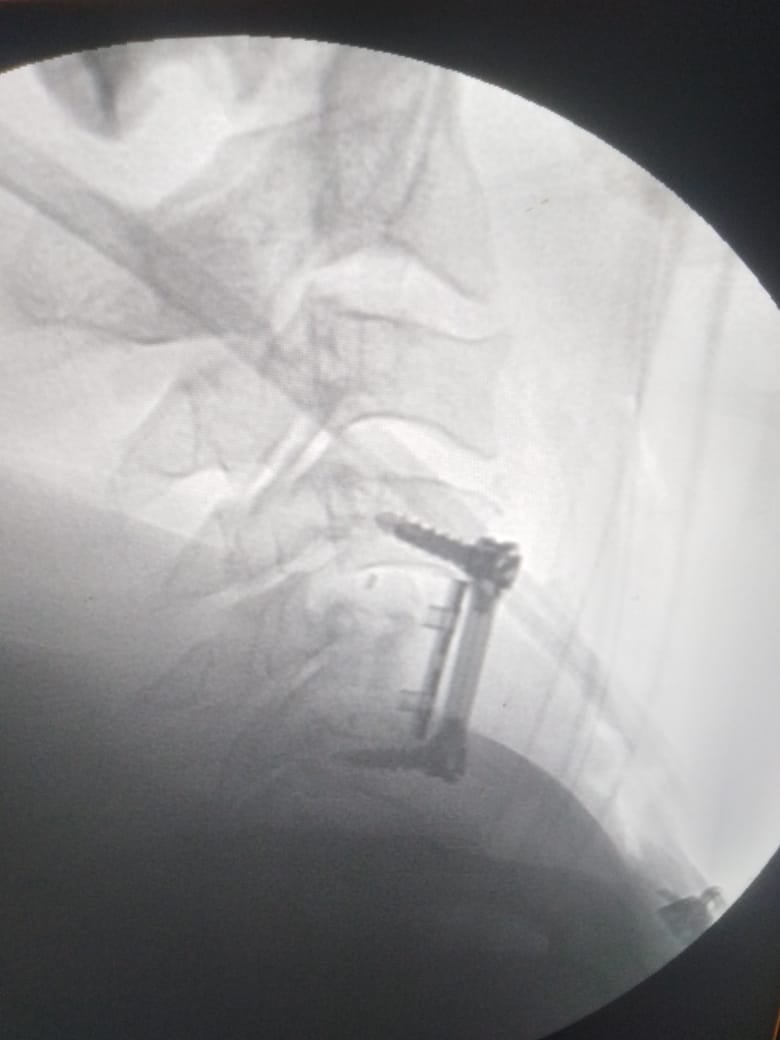

وشهدت الجراحة استئصال الفقرة الخامسة «المفتتة» ووضع دعامة عنقية وتثبيتها بواسطة شريحة ومسامير وتوسيع القناة العصبية.

وشارك الدكتور أحمد الرحماني، في إجراء الجراحة بمعاونة هدى فتوح، ومينا عاطف، فني الأشعة.